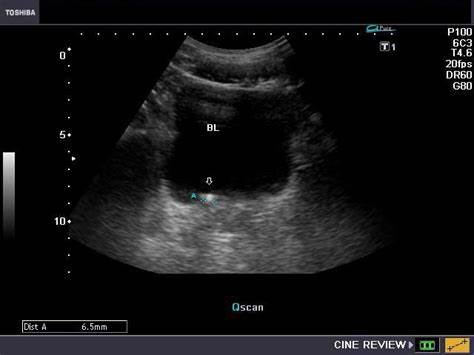

泌尿系结石

末端的输尿管结石会刺激膀胱三角区,刺激患者反复排尿。那么有人就要问了,为什么我不疼呢?结石梗阻以后,一般会引起急性疼痛,但是随着梗阻时间的延长,这种疼痛症状就会明显好转。同时老年人针对疼痛的耐受性较好,有的时候就会忽视掉这个问题。石头嵌顿在输尿管的末端,这个位置会刺激到我们的膀胱三角区,会刺激我们反复排尿,出现尿频尿急这些不同于典型输尿管结石的临床症状。

末端输尿管结石容易引起排尿症状